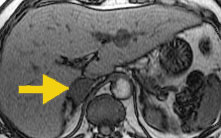

In this T1-weighted image, where fat and water signals are additive, the adrenal metastasis (arrow) is slightly less intense than in the adenoma above.

In this T1-weighted "opposed phase" imager, the adrenal metastasis (arrow) has the same signal intensity as in the in-phase image to the left. This is because the metastasis does not contain fat.